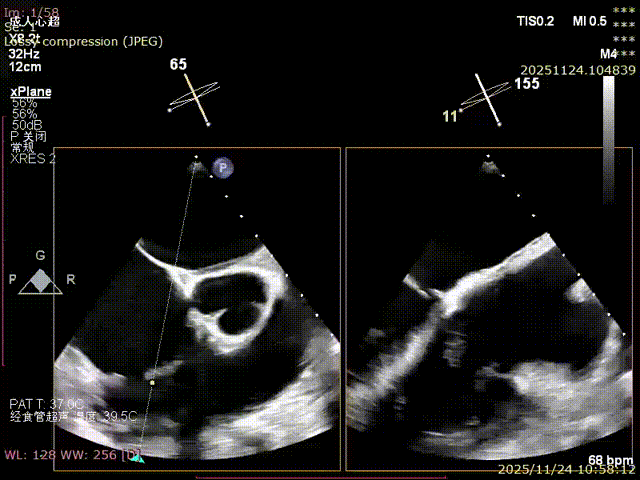

During the procedure, close collaboration was maintained with Dr. Yang Yan (anesthesiologist, Department of Anesthesiology) and Dr. Niu Ming (echocardiography specialist, team of Director Zhai Hong, Department of Cardiac Ultrasound). Guided by transesophageal echocardiography and assisted by DSA imaging, the tricuspid annular structure and regurgitation jet direction were precisely assessed. Ultimately, two 12T K-Clip® devices were successfully implanted. Immediate postoperative echocardiographic evaluation showed a significant reduction in tricuspid regurgitation from 4+ preoperatively to 1+, with a marked decrease in annular area. The surgical outcome was satisfactory.

Echocardiographic: Severe tricuspid regurgitation (grade 4+), with the regurgitant jet mainly located at the posteroseptal and central regions. No significant dilatation of the tricuspid annulus is observed. Mild myxomatous degeneration of the tricuspid leaflets is present, showing Barlow-like morphology, with leaflet prolapse of 3.7 mm in height.

Preoperative Regurgitation: 4+

Annulus Area: 11.3 cm²

Postoperative Regurgitation: 1+

Annulus Area: 4.9 cm²